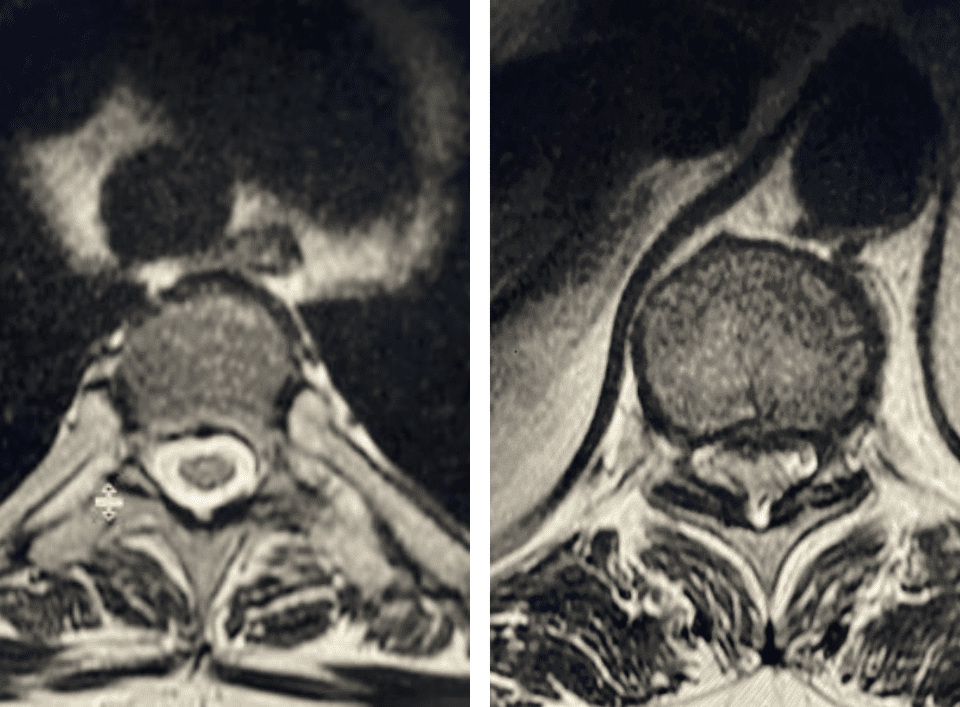

The spinal synovial cyst is one of the most interesting expressions of spinal instability. They emanate from the synovial lining of a degenerated facet joint that […]

People are obsessed with cysts! When you think about it, the body likes to form cysts. Why does this happen? Cysts can form just about anywhere […]